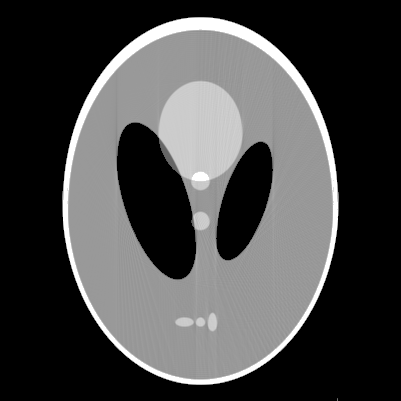

In this section, we will validate the performance of the proposed method by numerical experiments.

For this purpose, a SPECT version of the Shepp-Logan phantom(see figure 1(a), [1]) was used under various conditions.

Table 1 gives a description of the ellipses that form this phantom.

The attenuation map we used is equal to a constant inside the ellipse shown in figure 1(b). Although we used different values in the ellipse for different experiments to test the stability of the proposed methods, we only illustrate the reconstructed images in figures 2 and 3 for and , which are sufficiently large

for the medical applications of SPECT(see [1] for details).

The proposed method was performed for various computer-simulated data, including perfect, noisy, non-truncated and truncated data. Figure 2 displays the reconstructed images from perfect data, while figure 3 displays the reconstruction from noised data for and . The images in top row are reconstructed from non-truncated projection data, while these in the bottom row are reconstructed from the truncated data such that any measurement corresponding to a line not passing through the rectangular box in figure 1(a) was discarded.